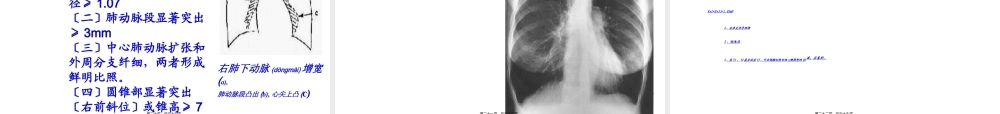

第五章呼吸系统(hūxīxìtǒnɡ)疾病第五节第一页,共三十九页。病因(bìngyīn)发病(fābìng)机制预后(yùhòu)临床表现实验室及其他检查诊断及鉴别诊断治疗概述慢性肺源性心脏病第二页,共三十九页。慢性(mànxìng)肺源性心脏病定义(dìngyì):由于肺组织、肺动脉血管或胸廓的慢性病变引起肺组织结构和功能异常,产生肺循环阻力增加,肺动脉高压,使右心室肥厚、扩大,伴或不伴右心衰竭的心脏病。第三页,共三十九页。慢性肺脏疾病肺动脉高压右心肥厚、扩大,右心衰竭慢性(mànxìng)肺源性心脏病第四页,共三十九页。慢性(mànxìng)肺源性心脏病患病年龄多在40岁以上,随年龄增长患病率增高。发病率为4.42‰,占≥15岁人群的6.72‰。北方>南方,农村>城市,吸烟者>不吸烟者,男女(nánnǚ)无差异。急性发作以冬、春季多见,气候急骤变化致急性呼吸道感染常为急性发作的诱因,常导致肺、心功能衰竭,病死率较高。占住院心脏病的46%-38.5%。流行病学:返回第五页,共三十九页。慢性(mànxìng)肺源性心脏病三大病因:一、支气管--肺疾病二、胸廓(xiōngkuò)运动障碍性疾病三、肺血管疾病及其他返回第六页,共三十九页。慢性(mànxìng)肺源性心脏病肺动脉高压形成缺氧性肺小动脉痉挛高碳酸血症的作用肺血管床面积减少血液流变学异常及血容量增加心脏负荷增加,心肌受损多脏器(zānqì)ɡ损害第七页,共三十九页。慢性(mànxìng)肺源性心脏病〔一〕缺氧性肺小动脉痉挛:缺氧平滑肌细胞膜对Ca2+通透性增加,细胞内Ca2+含量增高肌肉兴奋--收缩偶联效应增强(zēngqiáng)肺血管收缩ATP依赖性K+通道开放一、肺动脉高压形成第八页,共三十九页。慢性(mànxìng)肺源性心脏病〔二〕高碳酸血症的作用:高碳酸血症时,H+过多,使血管对缺氧收缩(shōusuō)敏感性增强。一、肺动脉高压形成第九页,共三十九页。慢性(mànxìng)肺源性心脏病〔三〕肺血管床面积减少:反复炎症使肺细小动脉狭窄、纤维化肺气肿压迫肺泡毛细血管(máoxìxuèuǎn)ɡ肺泡壁破裂后毛细血管网受损肺血管收缩和肺血管的重构一、肺动脉高压形成第十页,共三十九页。肺动脉高压(gāoyā)引起肺小动脉壁闭塞第十一页,共三十九页。慢性(mànxìng)肺源性心脏病〔四〕血液流变学异常及血容量(róngliàng)增加一、肺动脉高压形成第十二页,共三十九页。慢性(mànxìng)肺源性心脏病•肺动脉持续高压→右心肥厚;急性感染、病情开展使肺动脉压力继续增高→右心失代偿:右心扩...